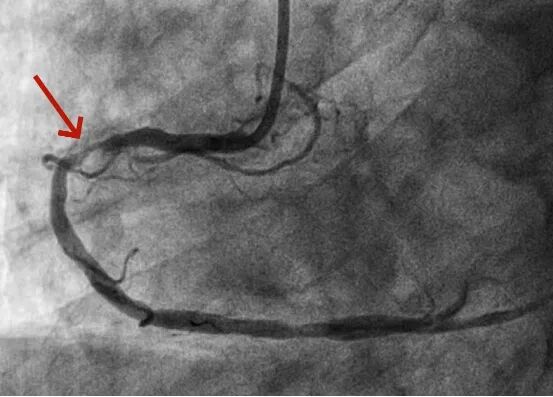

【山好水好人更好】州医院成功抢救七旬东北突发重症游客